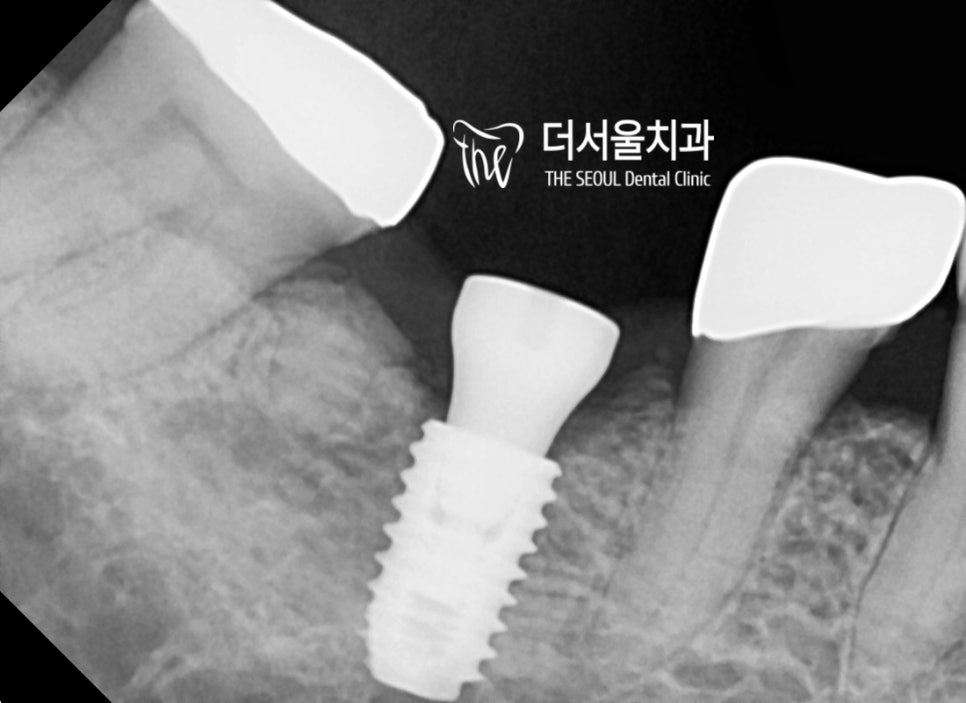

5분 정도 흘렀나..?

디지털 임플란트 식립이 끝났습니다.

이후 최종 보철과

양옆에 있는 크라운 제작까지

마무리했는데요.

변화된 모습을 보고 놀라지 마십쇼.

집 리모델링을 한 듯

예쁘게 심어져 있는 모습이네요~